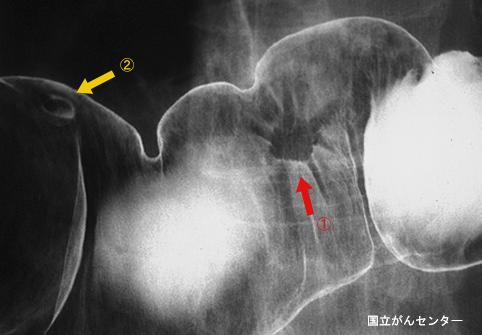

疾患(病理主体)の分類悪性上皮性腫瘍/腺癌

部位(臓器別)大腸/横行

検査方法X-P

腫瘍の肉眼分類0型(表在型)/I型(Is)

病変の最大径(ミリ)10〜14

腫瘍の深達度sm